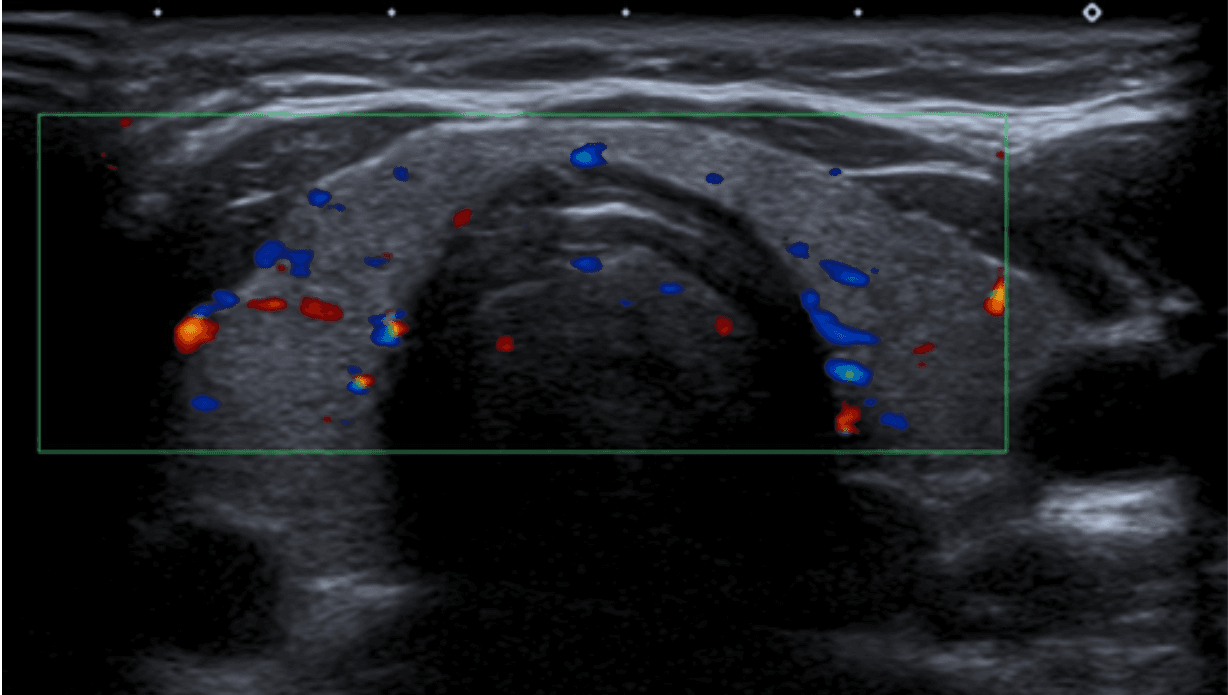

Vascularización tiroidea normal en Doppler color. Este patrón basal, con flujo conservado y velocidades picosistólicas de 20–40 cm/s, es la referencia indispensable para distinguir hiperfunción, inflamación y autoinmunidad en la patología tiroidea difusa.

Cuando la clínica es ambigua, la ecografía con Doppler se convierte en la herramienta decisiva para distinguir las dos grandes entidades autoinmunes. En la tiroiditis de Hashimoto, el patrón clásico combina aumento difuso de la glándula, múltiples micronódulos hipoecogénicos rodeados por septos finos hiperecogénicos, conocido como patrón en jirafa, además de nódulos sólidos hiperecogénicos tipo white-knight. Aunque puede existir hipervascularización, las velocidades picosistólicas suelen mantenerse en rangos no francamente elevados. En la enfermedad de Graves-Basedow, en cambio, la firma diagnóstica es el infierno tiroideo: hipervascularización difusa y marcada, acompañada de velocidades picosistólicas claramente elevadas, en general por encima de 60 a 70 cm/s. La diferencia no es solo estética. Es hemodinámica, funcional y terapéutica.

La tiroiditis de Hashimoto desplaza la interpretación tiroidea desde la lesión focal hacia el reconocimiento de un patrón difuso con firma propia. En Doppler color, la combinación de ecoestructura heterogénea, micronódulos hipoecogénicos rodeados por bandas lineales hiperecogénicas y vascularización no marcadamente aumentada construye un fenotipo ecográfico de alto valor diagnóstico. Para el radiólogo, esta imagen resume una enseñanza clave: no toda glándula heterogénea hipervascular corresponde a Graves; en Hashimoto, la arquitectura parenquimatosa sigue siendo el dato rector y el Doppler actúa como herramienta de precisión para evitar sobreinterpretaciones hemodinámicas.

Uno de los errores más frecuentes en imagen tiroidea es asumir que el aumento difuso de tamaño y la hipervascularidad visual bastan para concluir Graves. No siempre es así. Hashimoto puede simular actividad vascular aumentada, y solo la cuantificación Doppler permite separar un patrón linfocítico crónico de una tirotoxicosis franca. En este punto, la medición supera a la impresión cualitativa. El valor del Doppler espectral no está solo en confirmar flujo: está en objetivar comportamiento biológico.